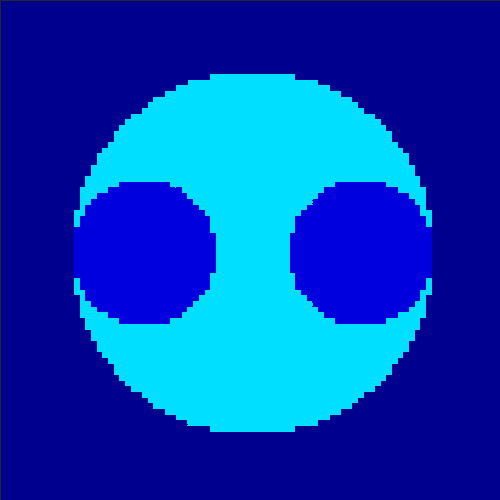

5.2 Monte Carlo Simulation

In order to test the behaviour of the proposed method in a more realistic, random-based test case, we performed a Monte Carlo simulation for dynamic SPECT imaging. First, we created a simple image phantom consisting of an outer and two inner circles which represents the structure of the region of interest (see figure 8(a)). Within those regions we assumed concentration curves over a time period of 90 time steps as displayed in figure 8(b). Based on the tracer intensity in an image frame at each time step, we created a variable number of random decay events (where the number is proportional to the average concentration in one pixel in the whole image frame per time step) with a probability proportional to the concentration in every subregion. They are detected by a virtual double head gamma camera rotating around the patient by 46 degrees per time step, which consists of 374 detector bins. Every simulated decay event is projected onto the scanner and counted by the corresponding detector bin.

In two different tests we fixed the number of events counted by the detector equal to (resp. ) times the average concentration in one pixel. The resulting sinogram images of the accumulated counts in each bin are shown in figure 9.

Based on the sinogram data we applied the proposed algorithm in order to reconstruct the original image sequence. The results for both test cases are shown in figure 10.

As one can see, the method is able to reconstruct the regions properly, even in case of a low count number. Within a number of iterations (average of 100 outer and 10000 inner iterations), the algorithm presents a reasonable reconstruction of the region of interest and the corresponding regional tracer concentration curves. Here, the parameters were not optimized as in the case of the synthesized data sets in the previous section, but kept fixed as , and . With futher optimized parameter values one could possibly provide even better results.